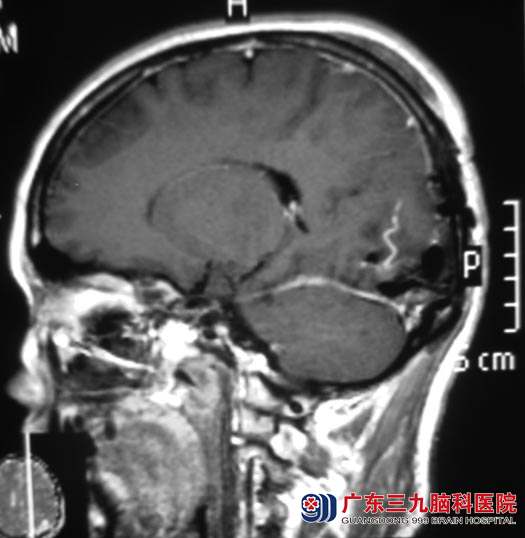

广东三九脑科医院进一步头颅MR检查:左侧枕部示一类圆形占位性病变,大小约41.7mm×53.1mm×52.1mm,左侧颞枕叶脑组织受压。

11月6日,综合神经外科 鲁明主任主刀,在全麻下行左侧枕部窦汇处脑膜瘤切除术。显微镜下见灰白色肿瘤,质中偏硬,血供丰富,先电灼、分离肿瘤基底部,再分块分离切除肿瘤,见肿瘤侵入窦内,分离、切除左侧窦内残留肿瘤,手术顺利。手术后阿珍头不晕,食欲基本恢复。病理结果为:过渡型脑膜瘤(WHO I级)。